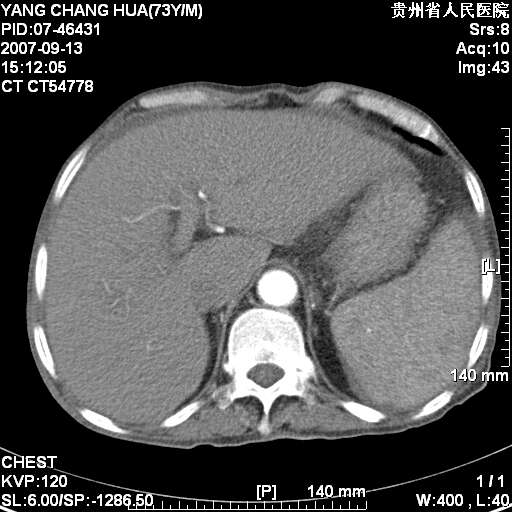

图像没有传全。肺部为感染性病灶;肺囊肿;双侧胸腔积液;肝脾肿大;腹水。

双肺部为感染性病灶.双侧胸腔积液;肝脾肿大;腹水.

双肺部为感染性病灶.双侧胸腔积液;肝脾肿大;脾脏密度不均,不除外脾侵润?腹水.

肝脾肿大。

少量腹水。

双肺散在斑片状及多发小结节状阴影,边缘模糊,双上肺野明显,双侧胸膜腔少量积液,纵隔及肺门区未见明显肿大淋巴结,肝脾肿大,脾内见多发低密度区,结合临床考虑恶性淋巴瘤(肺内表现为肺炎肺泡型),单看影像表现,肺结核不能排除。建议结合实验室检查或表浅淋巴结活检。